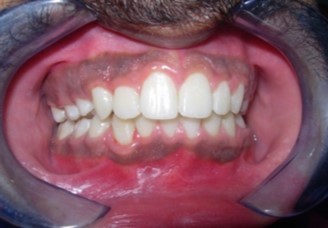

Results

The soft tissue frontal and profile improved dramatically. (Figure 7a-b). The bilateral posterior crossbite was corrected. The severe increase in overjet of about 13mm was effectively reduced to 3mm and the severe deep bite was also corrected (Figure 7c,Figure 7d). Fixed maxillary and mandibular lingual retainers were given. (Figure 7e, Figure 7f). Post orthodontic treatment, normal root inclinations of the teeth and normal alveolar bone levels was observed. (Figure 8).

Figure 7c.Post-treatment intra-oral-Frontal

Figure 7d.Post treatment intra-oral – Right